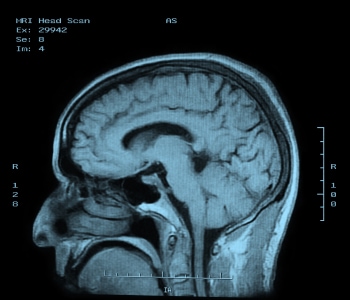

Magnetic resonance imaging (MRI) is a completely different way of viewing inside parts of the body. It relies on the way hydrogen nuclei respond to magnetic fields. Functional MRI (fMRI) is a specialized version used in the brain, tracking oxygen instead to image blood flow based on oxygenation levels.

This process works by placing the body in a strong static magnetic field so that all the nuclei are oriented in the same direction. A varying field is then created to perturb the atoms locally; this re-orients them from their starting position. When that varying field is removed, the cell processes back to the static position. Different cells relax at different rates, ranging from tens of milliseconds to over one second, and the decay signals given off as the cells move back – in the 1 to 300 MHz range – create the image (see Figure 5). It is these differences in the relaxation timing that allow the system to discriminate different kinds of tissues.

Figure 5: MRI image of the brain.